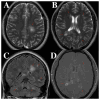

The diagnosis of acute disseminated encephalomyelitis (ADEM) is challenging due to the existence of other medical conditions that mimic its symptoms and the lack of precise biomarkers. Timely diagnosis is essential for commencing an appropriate treatment, which enhances the clinical trajectory and long-term prognosis. The purpose of the present study was to emphasize significant concerns, specifically for neurologists and radiologists, due to the difficulties involved in identifying this disorder. Neurologists must have an extensive understanding of the clinical manifestations and constraints of current diagnostic tests. Furthermore, this understanding is equally essential for radiologists, as it serves as the foundation for precise diagnostic interpretations derived from imaging findings. The intricate nature of neurological disorders frequently necessitates a cooperative effort between neurologists and radiologists to guarantee precise diagnosis and efficient therapy strategizing. The present study discusses a case of a male patient who was diagnosed with ADEM based on clinical, biological and imaging evaluations.